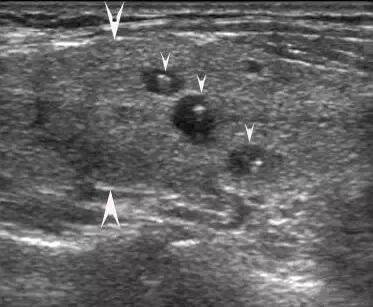

大箭头指向腺体,小箭头指向结节,结节外腺体回声不均

大箭头指向腺体,小箭头指向结节,有的结节伴弧形钙化,结节外腺体回声不均。